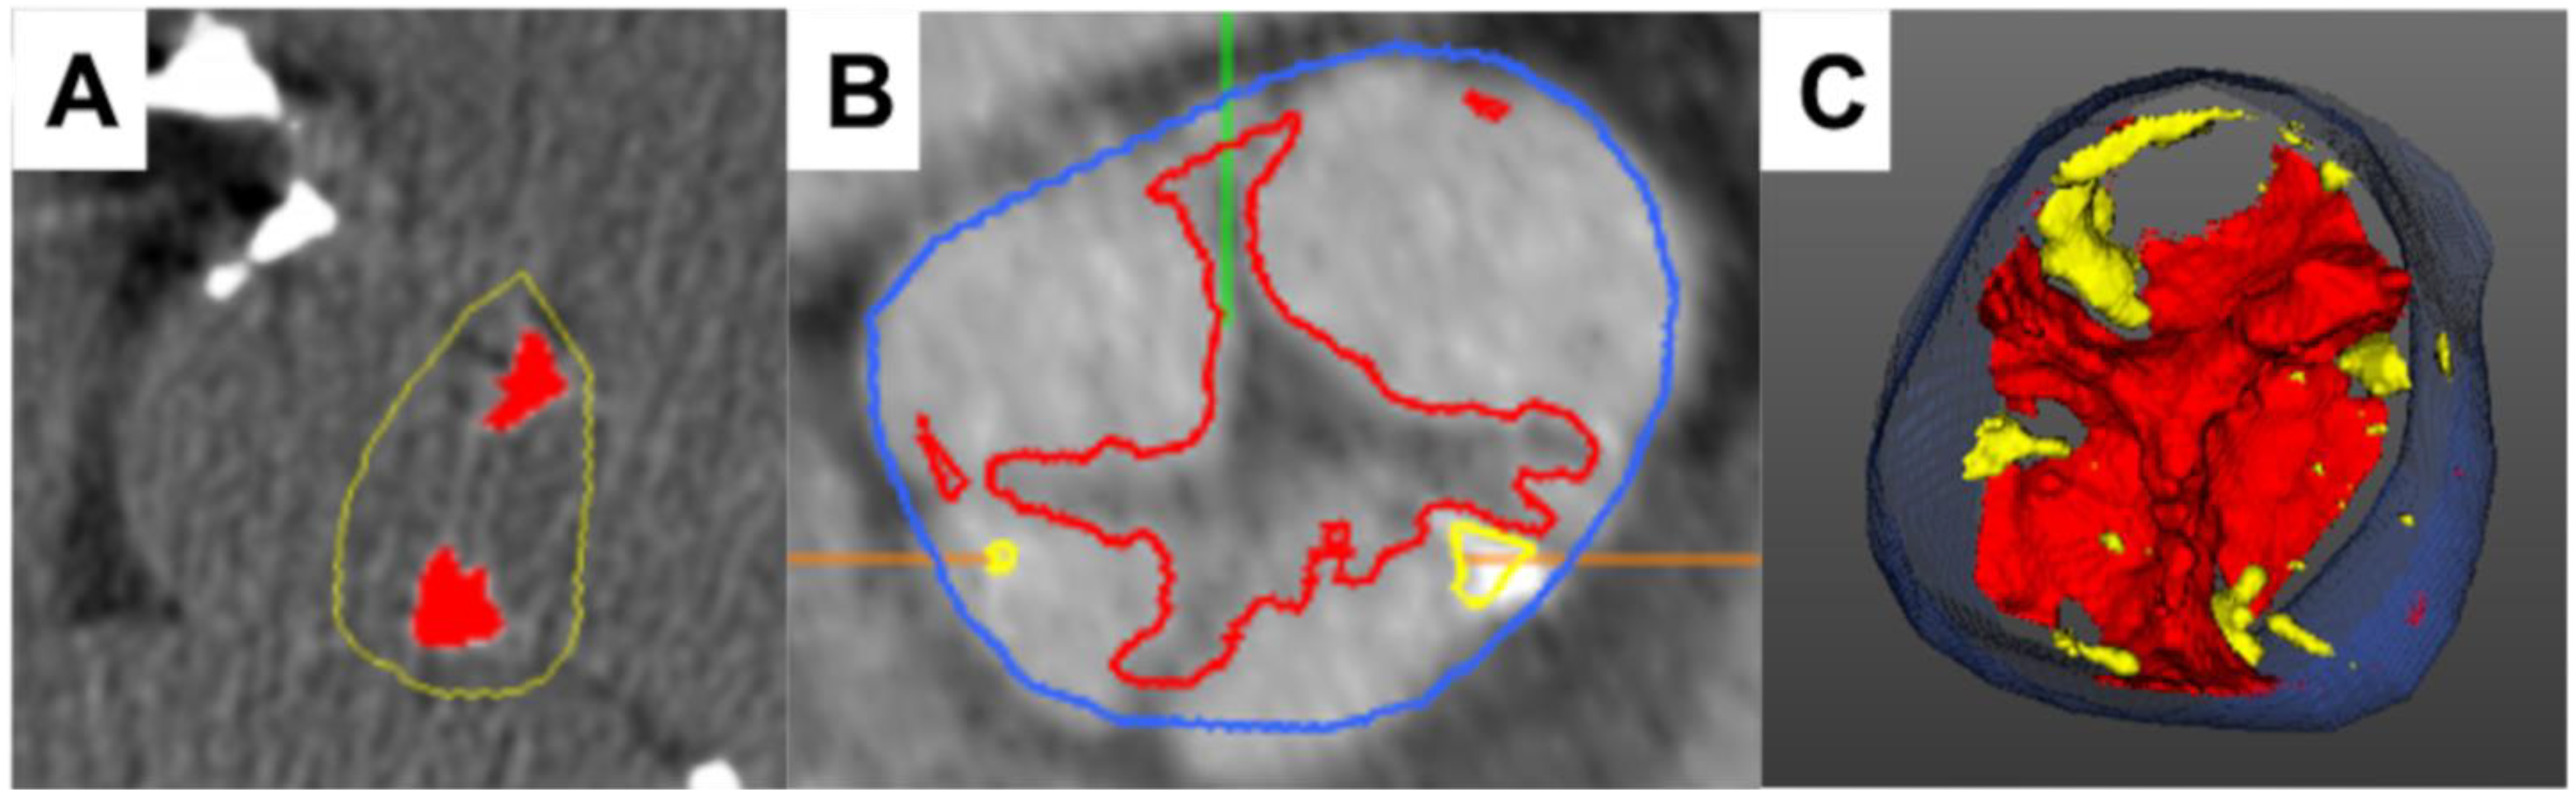

- Grodecki, K.; Tamarappoo, B.K.; Huczek, Z.; Jedrzejczyk, S.; Cadet, S.; Kwiecinski, J.; Rymuza, B.; Parma, R.; Olasinska-Wisniewska, A.; Fijalkowska, J.; et al. Non-calcific aortic tissue quantified from computed tomography angiography improves diagnosis and prognostication of patients referred for transcatheter aortic valve implantation. Eur. Heart J. Cardiovasc. Imaging 2021, 22, 626–635. [Google Scholar] [CrossRef]